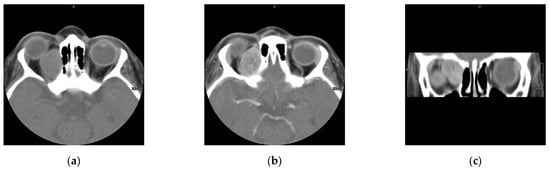

The scans at diagnosis showed masses with hypodense contrast enhancement of the tumor in all cases, with a pattern of generalized enhancement (see Figure 1). MRI at diagnosis showed low signal (isointense or hypointense) of soft tissues on T1-weighted images and high signal (hyperintense) on T2-weighted images, and gadolinium enhancement in all cases (see Figure 2). The tumor border was smooth (in 77% of cases), lobulated (10%), or mixed (13%) (see Figure 3). No association was found between tumor border type and recurrence rate or death.

Figure 1. Computed scan tomography (CT) of orbital RMS case: non contrast axial section (a), contrast axial section (b), and contrast coronal section (c). This case shows a hypodense lesion on CT with post-contrast enhancement.